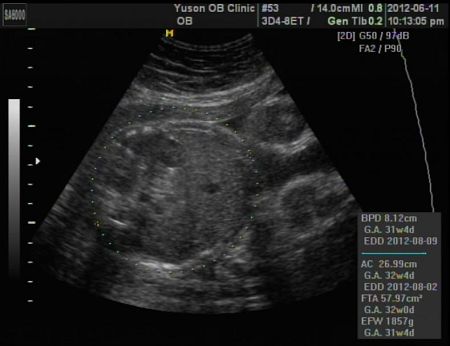

1859G

頭圍、體重、腳長,都是正常,快點!再一個多月!我快等不及啦!